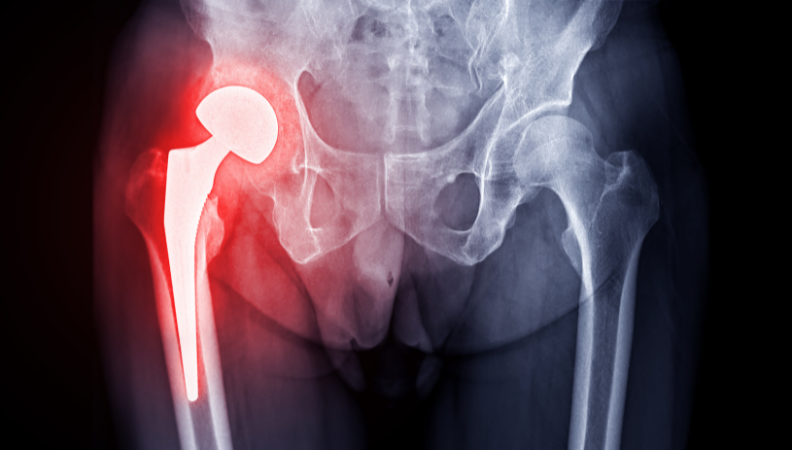

Total Hip Replacement (THR), also known as hip arthroplasty, is a surgical procedure in which a damaged or worn-out hip joint is replaced with an artificial implant. It is commonly recommended for patients with severe arthritis, hip fractures, or chronic hip pain that limits movement and daily activities.

We offer a full spectrum of hip surgeries, including total hip replacement, partial hip replacement, and revision hip surgery for failed or worn implants.

Our minimally invasive hip replacement techniques reduce blood loss, minimize scarring, and enable quicker return to daily life.